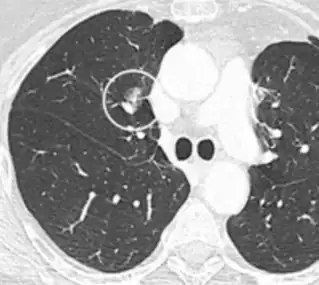

subpleural nodule.[9]

Round well-delineated solid lung nodule with smooth border.[9]

Lobulated nodule.[9]

Spiculated lung nodule.[9]

A "notch sign".[9]

A triangular perifissural node can be diagnosed as a benign lymph node.[9]